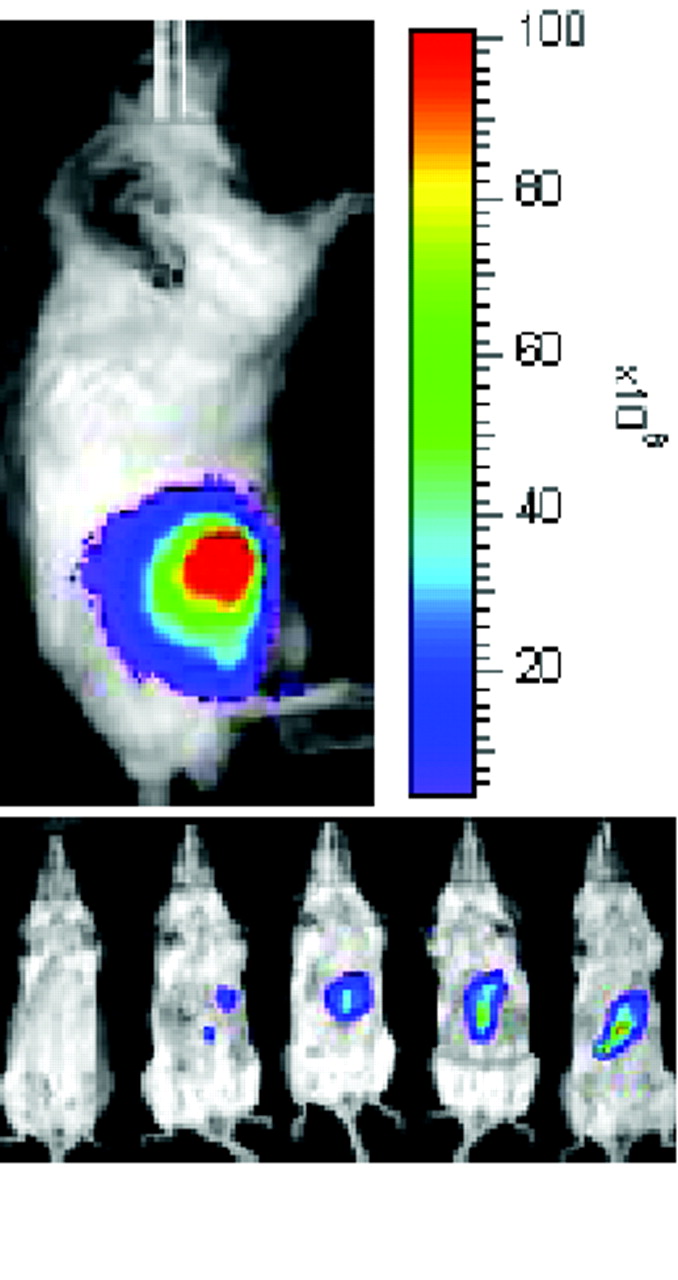

The spectrum of neuroimaging techniques: Specialization and complementarity. All imaging technologies utilize specific electromagnetic wavelengths to generate and measure signals. MRI utilizes radio frequencies at the far right of the electromagnetic spectrum and maintains a high static magnetic field to produce images of high spatial resolution. MRI provides anatomical and some physiological imaging. In contrast, fluorescence/bioluminescence and near-infrared optical imaging utilize visible or near-visible wavelengths to produce images of high sensitivity relatively quickly, but the spatial resolution is lower than that provided by MRI. In vivo optical imaging can provide additional information at the molecular level. More energetic and shorter wavelengths are employed in X-ray and CT scanning, which provide excellent anatomical images of high sensitivity but little information at the molecular level. PET and SPECT imaging, which utilize very short wavelengths—in the gamma range of the spectrum—provide excellent sensitivity and yield information about metabolism, molecular targets, and physiology, although spatial resolution may be better provided by other modalities. (See text for discussion of methods and modalities for translation into human studies and therapeutics.)